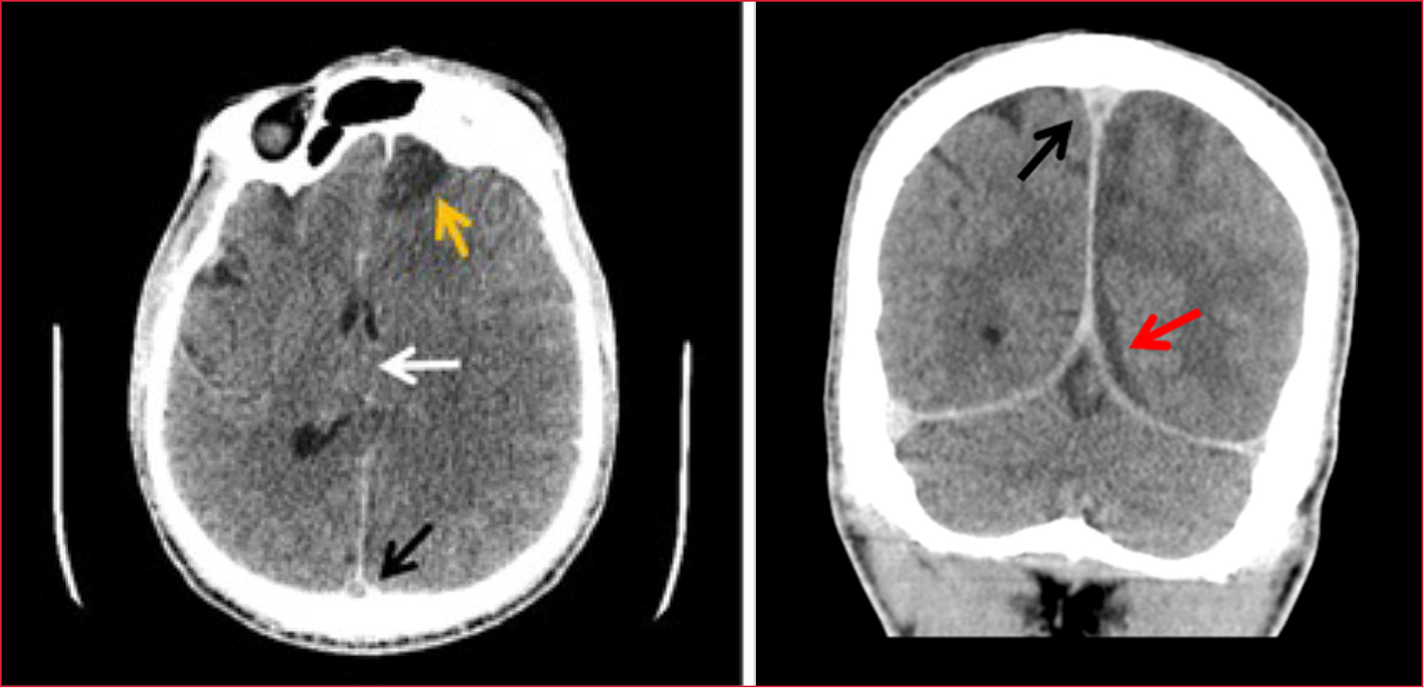

La segunda tomografía computarizada mostró una trombosis venosa extensa del seno longitudinal superior, colección subdural extensa laminar en el hemisferio izquierdo, lesión isquémica extensa frontoparietal izquierda con edema, efecto de masa y signos de herniación subfacial con desviación de la línea media. Se destacaba una sinusopatía crónica con comunicación directa entre el seno frontal izquierdo y la cavidad intracraneal como probable origen de los hallazgos radiológicos (Figura 2).

Figura 2. Trombosis venosa extensa del seno

longitudinal superior, signo del delta vacío, colección subdural laminar

extensa en el hemisferio izquierdo con edema, efecto de masa y signos de

herniación subfacial. Desviación de la línea media.